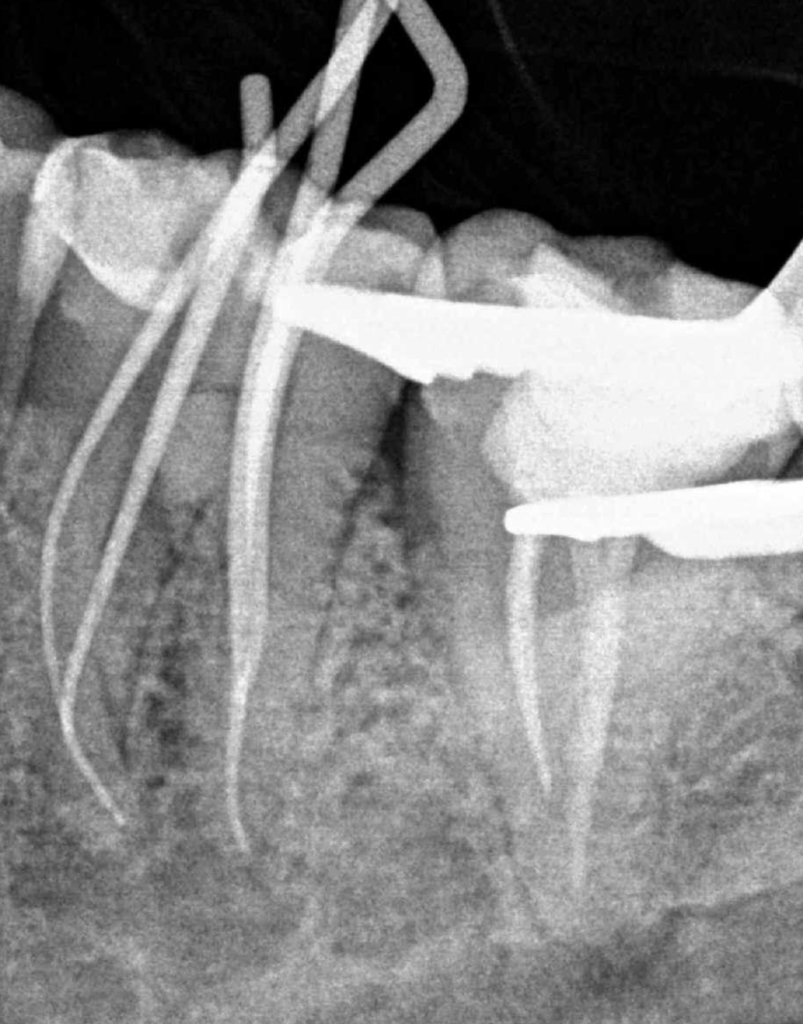

Fisura, remoción amalgama para explorar